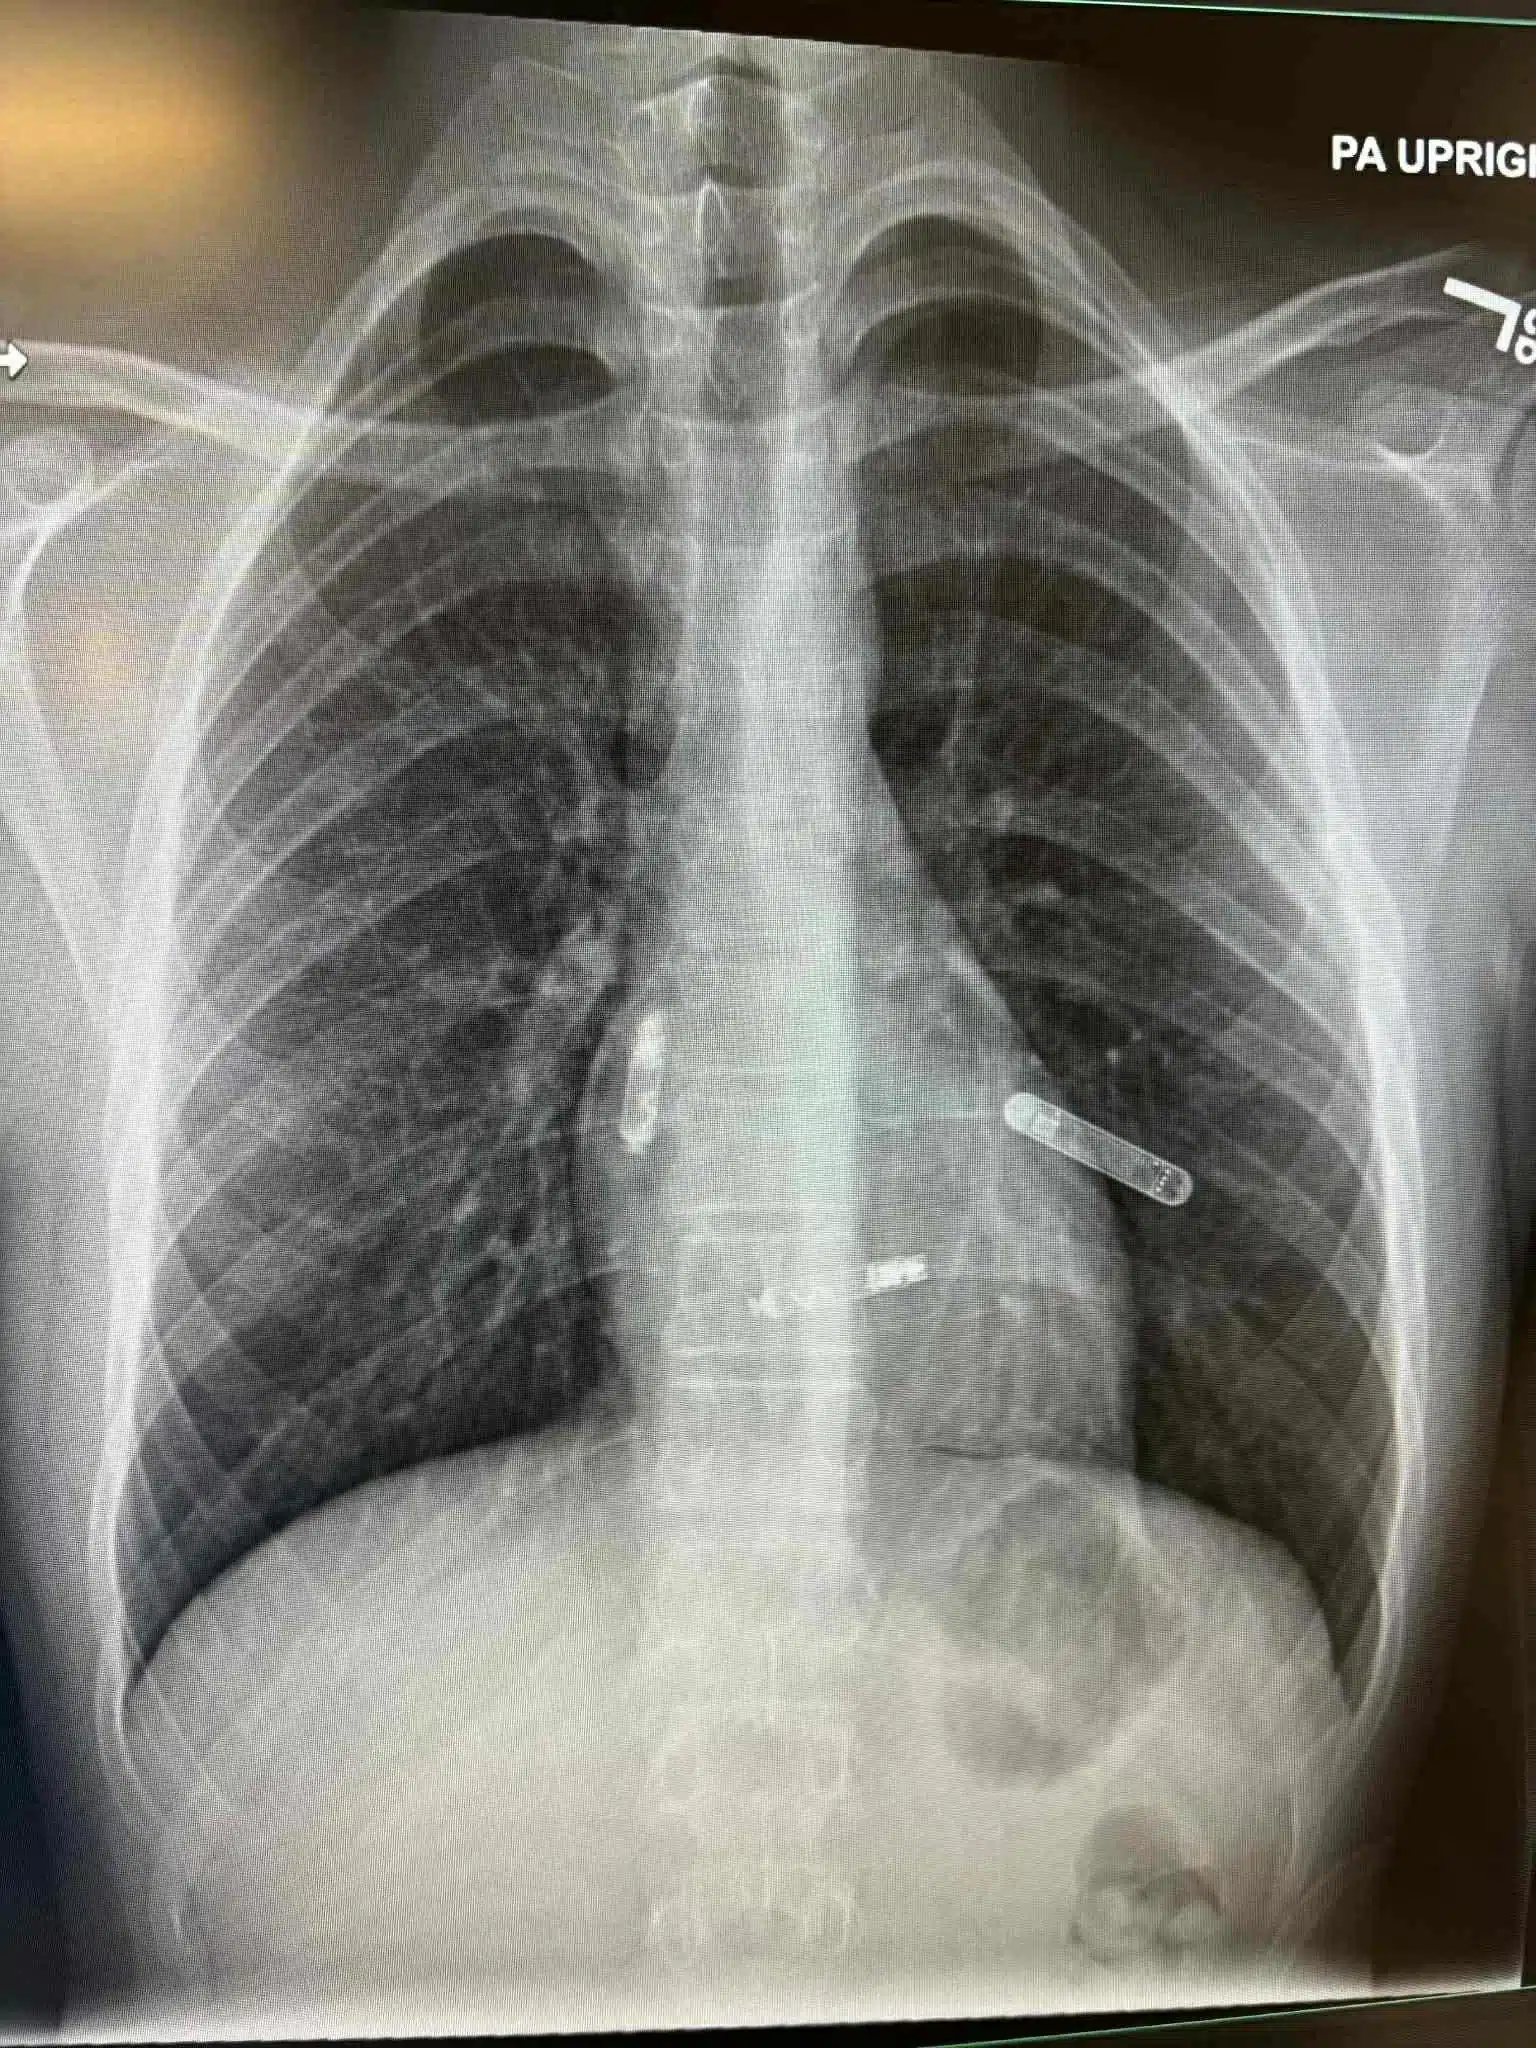

Prije par dana je u američkoj saveznoj državi Floridi izvedena revolucionarna kardiohirurška intervencija koja će ući u medicinsku historiju. Naša Mostarka, dr. Svjetlana Tišma-Dupanović, kardiologinja i pedijatrica, uspješno je pacijentu ugradila dvokomorni pejsmejker direktno u srčane šupljine — u pretkomoru i komoru — koji sinhronizovano stimulišu pravilan rad srca.

Ovo je prva takva operacija izvedena na Floridi, a ujedno predstavlja veliki napredak u liječenju bolesti srca, posebno za pacijente sa poremećajima srčanog ritma i slabijom pumpnom funkcijom srca.

Tradicionalni pejsmejkeri postavljaju se ispod kože grudnog koša, a žice prolaze kroz vene do srca. Nova tehnologija, koju je primijenila dr. Tišma-Dupanović, omogućava direktnu ugradnju uređaja unutar srca — bez žica koje prolaze kroz krvne sudove.

Ovaj dvokomorni (biventričularni) pejsmejker sinhronizuje rad pretkomora i komora, čime se postiže pravilniji ritam i veća efikasnost pumpanja krvi.

U medicinskoj terminologiji, ovakav zahvat spada u “srčanu resinkronizacijsku terapiju” (Cardiac Resynchronization Therapy – CRT), koja koristi više stimulacijskih tačaka za postizanje optimalne kontrakcije srčanog mišića.